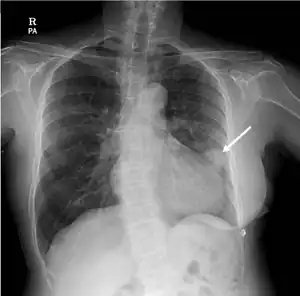

| Rounded, bulging mass in the superior cardiac border and adjacent lung nodule arrow on chest X-ray. | |